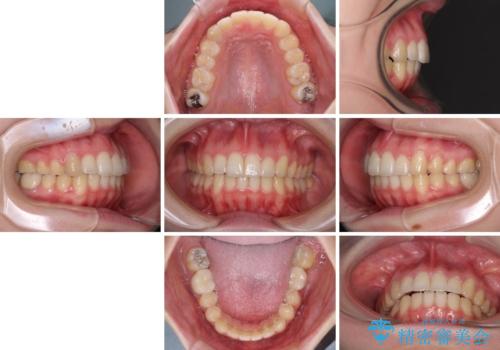

インプラント治療とインビザライン矯正治療 総合歯科治療

治療症例の内容

- 患者様

- 20代女性

- 矯正装置

- インビザライン

- 治療期間

- 3年1ヶ月

- 治療回数

- 10-30回

- 口の閉じにくさと割れてしまった奥歯を気にして来院された患者様です。

IPR(歯と歯の間を削る)と歯列全体の後方移動によって口元が引っ込むように設計し、インビザラインにより治療を行うこととしました。

割れてしまった奥歯は抜歯し、矯正治療中の良いタイミングでインプラントを埋入することとしました。

上下正中がずれていたため、抜歯による矯正治療も検討しましたが、口元がそれほど突出していなかったため、非抜歯にて矯正することになりました。

その結果正中のズレは残りましたが、口を閉じたときの感覚や奥歯の咬み合わせには全く問題なく、患者様には大変満足していただきました。